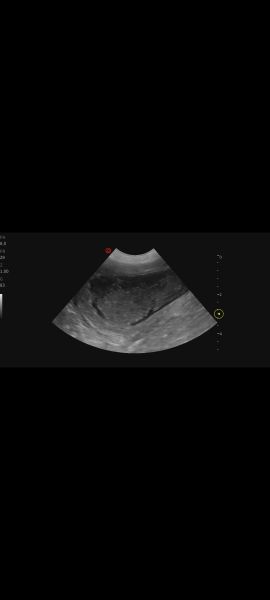

Hi, my vet performed an ultrasound on 7 year old lab mix because of an UTI .She said her bladder walls look thickened and spongy. She's concerned. Can you tell anything? I'll try to add more pics under commentsScreenshot_20251230_161511_PhotosScreenshot_20251230_161500_PhotosScreenshot_20251230_161447_Photos

Hello and thankyou for sharing these pictures.  Unfortunately we do not read ultrasound scans and cannot give out emergency advice or second opinions on this site; that is your vets responsibility. What clinical signs is your dog showing?